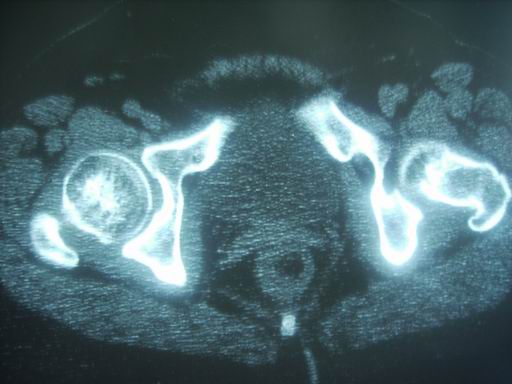

标题: CT19446:女性 右髋关节疼痛半年 近日加重 [打印本页]

标题: CT19446:女性 右髋关节疼痛半年 近日加重

考虑退行性变,不除外结核.

没有外伤史那那种\"骨折\"一样的东西要怎么解释呢,可能是退变,囊变引起的,扫描有点厚,不利于连续层面观察,结核暂放弃

考虑髋关节退变,不除外低毒力炎性肉芽致骨质改变!定期复查吧。

退变,关节软骨下囊变

考虑右髋关节退行性改变;不排除右侧髋臼慢性骨感染性病变。

考虑右侧髋臼慢性骨感染性病变。不除外关节软骨下囊变。

tb可能,转移瘤待排.